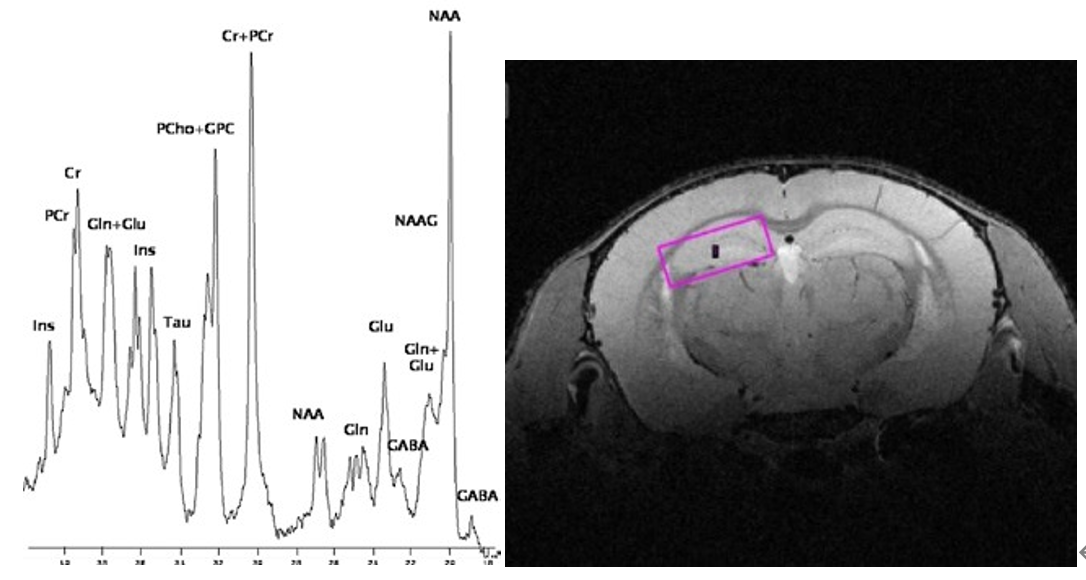

5、磁共振波譜

高強(qiáng)磁場(chǎng)下的磁共振波譜給研究腦部、腫瘤等代謝情況提供新的有效工具,布魯克卓越的活體定域譜技術(shù)實(shí)現(xiàn)小于10毫秒的回波時(shí)間,可以研究更廣泛的代謝物。精密的勻場(chǎng)算法減小譜峰的重疊,達(dá)到最好的波譜分辨力。

高強(qiáng)磁場(chǎng)下的磁共振波譜: